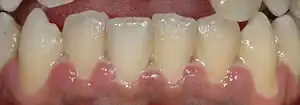

| A fairly mild presentation of acute necrotizing ulcerative gingivitis at the typical site on the gums of the anterior mandibular teeth. | |